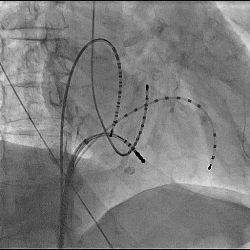

経皮的心筋燃焼灼術(カテーテル・アブレーション)の一例

-

- 【1】多発性心室性期外収縮に対しての一例

- 【2】発作性心房粗動に対しての一例